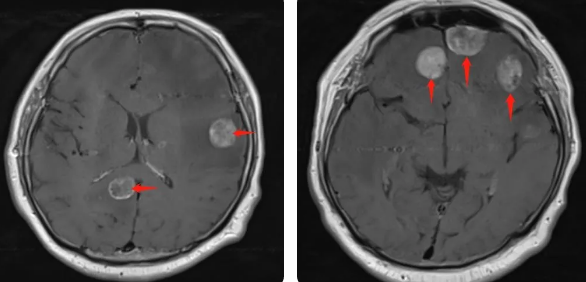

無獨(dú)有偶,60歲的左肺癌患者石先生,在外院接受了手術(shù)治療,結(jié)果術(shù)后10月出現(xiàn)腫瘤腦轉(zhuǎn)移,頭部增強(qiáng)MRI顯示:顱內(nèi)多發(fā)占位性病變伴水腫,接二連三的重?fù)糇屖壬霈F(xiàn)表情淡漠,沉默寡言,絕食等抑郁癥狀,VMAT放療技術(shù)與心理疏導(dǎo)雙管齊下,3周的治療后顱內(nèi)轉(zhuǎn)移病灶顯著縮小,部分甚至消失,困擾石先生的頭痛、頭暈癥狀也不復(fù)存在,石先生重拾對(duì)生活的希望,也對(duì)未來的治療充滿信心。